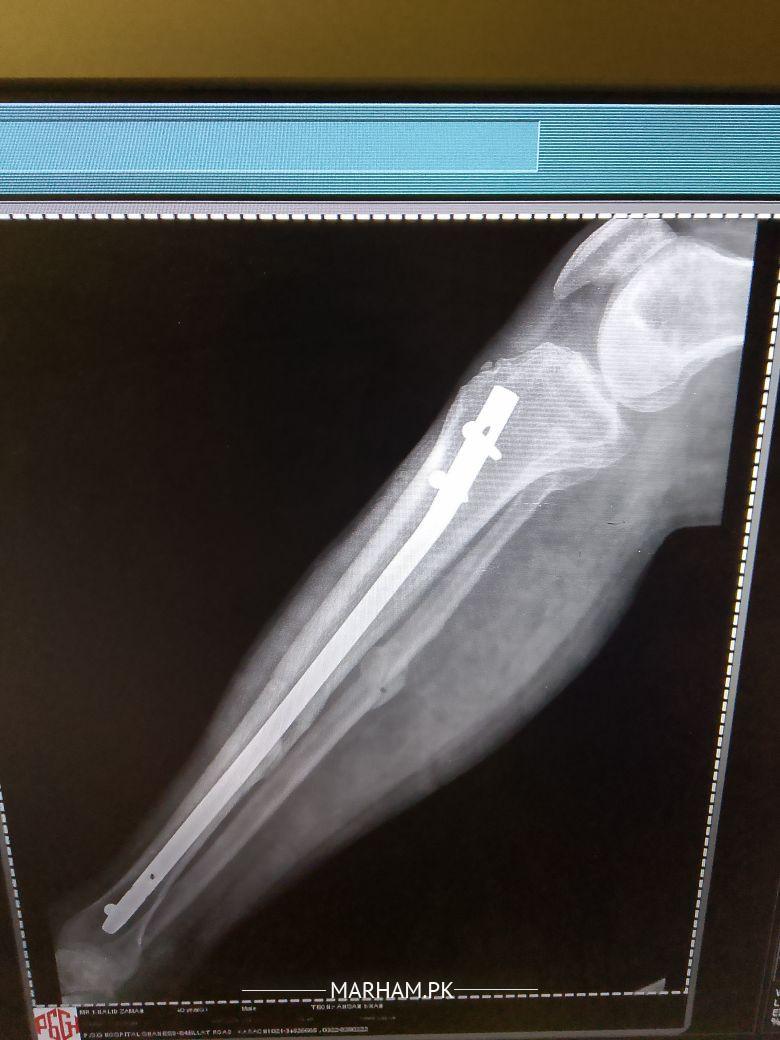

sir mane 5 month pehle opretion keya tha leg ka Lekin mere leg Mai abhi bhi pain ho Raha hai or baghir sahare k nai chal sakta sir plz check my report k Kya reason hai

seems like a case of delayed union. take vit d and calcium supplements and visit orthopaedic nearby. hopefully it will improve.

sir plz reply me k Kya Mai phir opretion karon? q k es Mai haddi ka ik piece hai jes se leg Mai soojan hothi hai or ik keel morh geya hai.plz reply me

Aap ki haddi poori tara se juri nai ay abhi jis ki waja se dard huta ay aapko koi peep waghera aati hai??

sir ye haddi ka Kya karon Jo ik chota sa peace hai